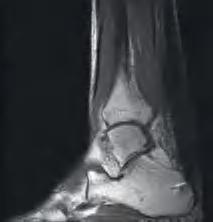

Rycina 6.16. Obraz RM – ewaluacja wyników leczenia pół roku po wykonaniu plastyki V-Y u pacjentki

przeszczepu.